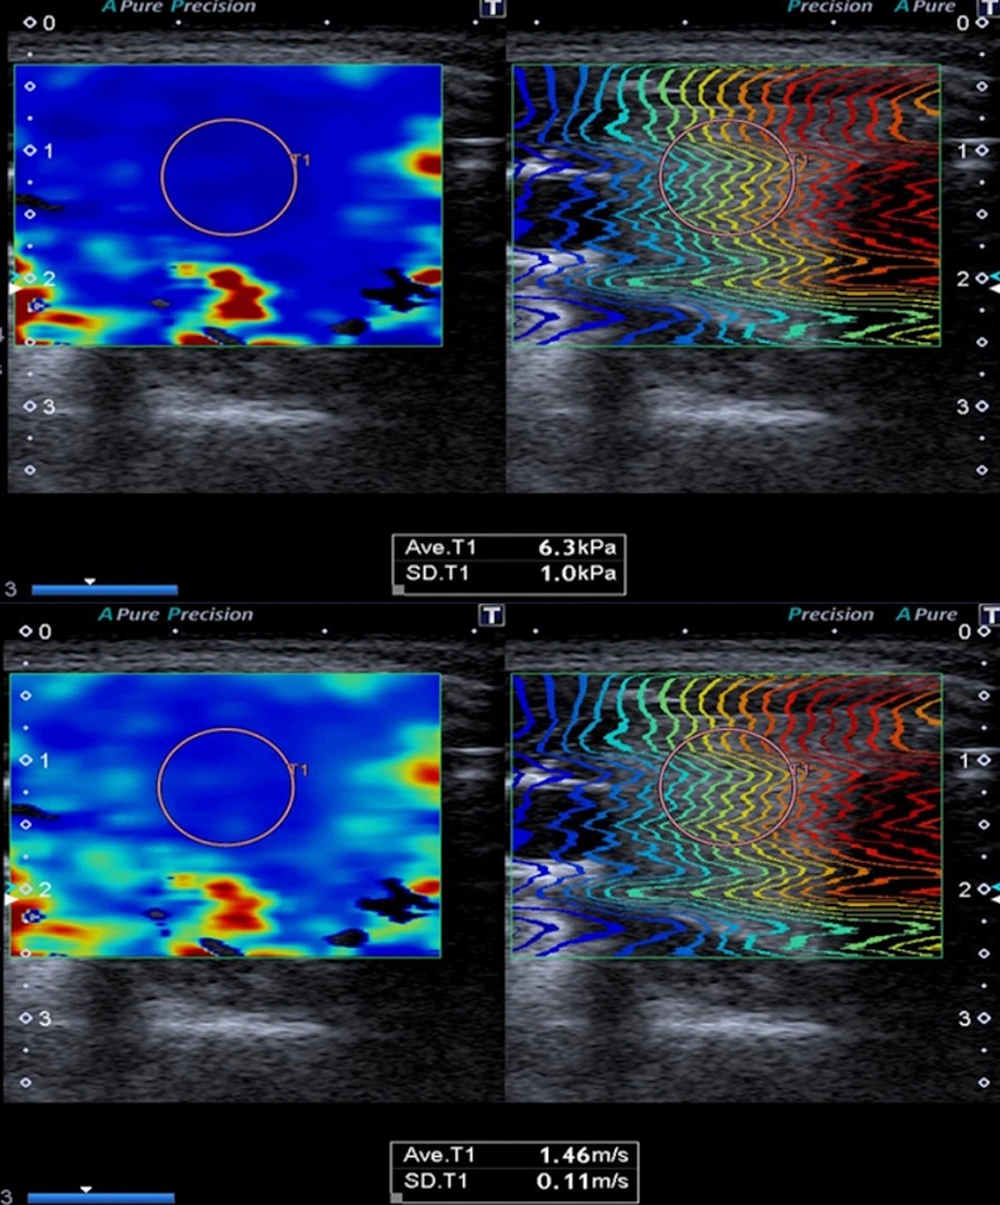

Ultrasonographic evaluation of the thyroid gland was conducted using a Canon Aplio 500 device (Canon Medical System Corporation, Tokyo, Japan) equipped with a high-frequency (6.2 - 12 MHz, center frequency: 8 MHz) linear transducer. The US examination was performed with the patient in a supine position and the head in slight extension. All measurements were made by a radiologist with eight years of experience in elastography. The dimensions of both thyroid lobes were individually measured in three planes (length × width × height) using gray-scale images. Thyroid lobe volume values were calculated automatically by the device (Figure 2). The thyroid gland was evaluated with B-mode US to examine parenchymal and nodular disease. Ensuring the parallelism of elastography lines in 2D-SWE measurements and utilizing a homogeneous color map to code the thyroid lobe were established as criteria for optimal measurement quality. The 2D-SWE measurements were obtained by outlining a circular region of interest (ROI) in the axial plane for each thyroid lobe. The ROI was accepted as between 5 × 5 mm and 10 × 10 mm, which would be from the region that meets the appropriate criteria (Figure 3). Elastography measurements were obtained from the central part of the parenchyma for each thyroid lobe. A minimum of three measurements were taken from elasticity (kPa) and velocity (m/s) images for each thyroid lobe, and the average of the recorded values was calculated. All measurements for each lobe were made from the same ROI at the same location. Measurements were made in the morning, under a fasting condition of at least 8 hours.

Repeated-measures ANOVA revealed significant overall effects of gestational age on several parameters, including 2D-SWE values, TSH, fT3, and fT4 levels. Although mean thyroid volume tended to increase with gestational age (9.72 ± 4.21 mL in the first trimester, 10.69 ± 4.55 mL in the second, and 11.75 ± 5.2 mL in the third), this change did not reach statistical significance (P = 0.1681). Mean 2D-SWE velocities (m/s) significantly decreased across trimesters, from 1.71 ± 0.10 in the first trimester (95% CI: 1.68 - 1.74) to 1.64 ± 0.08 in the second (95% CI: 1.62 - 1.66) and 1.60 ± 0.07 in the third (95% CI: 1.58 - 1.62) (P < 0.0001). Similarly, mean stiffness values (kPa) also declined progressively, with values of 8.98 ± 1.28 (95% CI: 8.61 - 9.35), 8.28 ± 1.18 (95% CI: 7.94 - 8.62), and 8.01 ± 1.16 (95% CI: 7.67 - 8.35) for the first, second, and third trimesters, respectively (P < 0.0001). This downward trend was consistently observed in both right- and left-sided measurements for velocity and kPa.

Various studies have presented varying ranges of elasticity (kPa) (9-19) and velocity (m/s) (1.2 - 2) values for the normal thyroid gland using the 2D-SWE method. Mean 2D-SWE values for the healthy control group were reported as 12.49 ± 3.23 kPa and 1.94 ± 0.23 m/s in the study by Kara et al., 10.97 ± 3.1 kPa in the study by Arda et al., and 9.5 ± 3.6 kPa in the study by Herman et al. (7, 27, 28). In our study, we computed the mean 2D-SWE values for all three trimesters among healthy pregnant women who exhibited no thyroid gland pathology on ultrasound and had normal laboratory findings. To our knowledge, no other studies are available in the literature that focus on thyroid gland elastography in pregnant women. Consequently, when compared to measurements from non-pregnant healthy control groups as documented in existing literature, the mean kPa and m/s values observed in our study for all three trimesters were marginally lower but remained within the realm of normal ranges. Furthermore, our study identified a decline in elastography values during the latter stages of pregnancy. As far as we know, decreased thyroid gland stiffness has only been reported in cystinosis cases in the literature. It has been reported that the reason for the decrease in tissue stiffness in these cases may be the loosening of extracellular matrix fibers and adhesions between cells, leading to a decrease in tissue stiffness (29). This situation in our study may be due to the changes mentioned above. Still, it may also be attributed to the fact that the enlargement of the thyroid gland during pregnancy may be associated with an increase in extracellular fluid and blood volume. We believe that with the widespread use of elastography in thyroid imaging, knowing the physiological elastography changes that occur during pregnancy and the normal elastography values for all three trimesters can prevent possible incorrect predictions, especially overdiagnosis, and increase the awareness of radiologists.